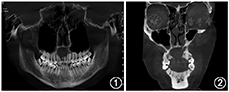

患者,女性,36岁,反复上颌前牙区肿胀疼痛1年,自服抗炎药物治疗(剂量不详),肿胀无明显消退,曾于当地医院拍摄CT示上颌骨肿物,未予处理。入院后拍摄CBCT示:13-22根尖区见大小约2.6 cm×1.8 cm大小的低密度影(图1, 图2)。患者既往健康,否认高血压、糖尿病病史,家族成员中否认类似病史。

口腔检查:上颌前牙区肿胀隆起,硬腭正中前部局部隆起,触软,其对应的唇侧略隆起,触之软感(图3)。前鼻镜检查:鼻腔黏膜略充血,右侧鼻底部略隆起。鼻内镜示:鼻黏膜充血,右侧前部鼻底部略隆起,鼻道通畅,鼻咽部未见明显异常。诊断:鼻腭囊肿。